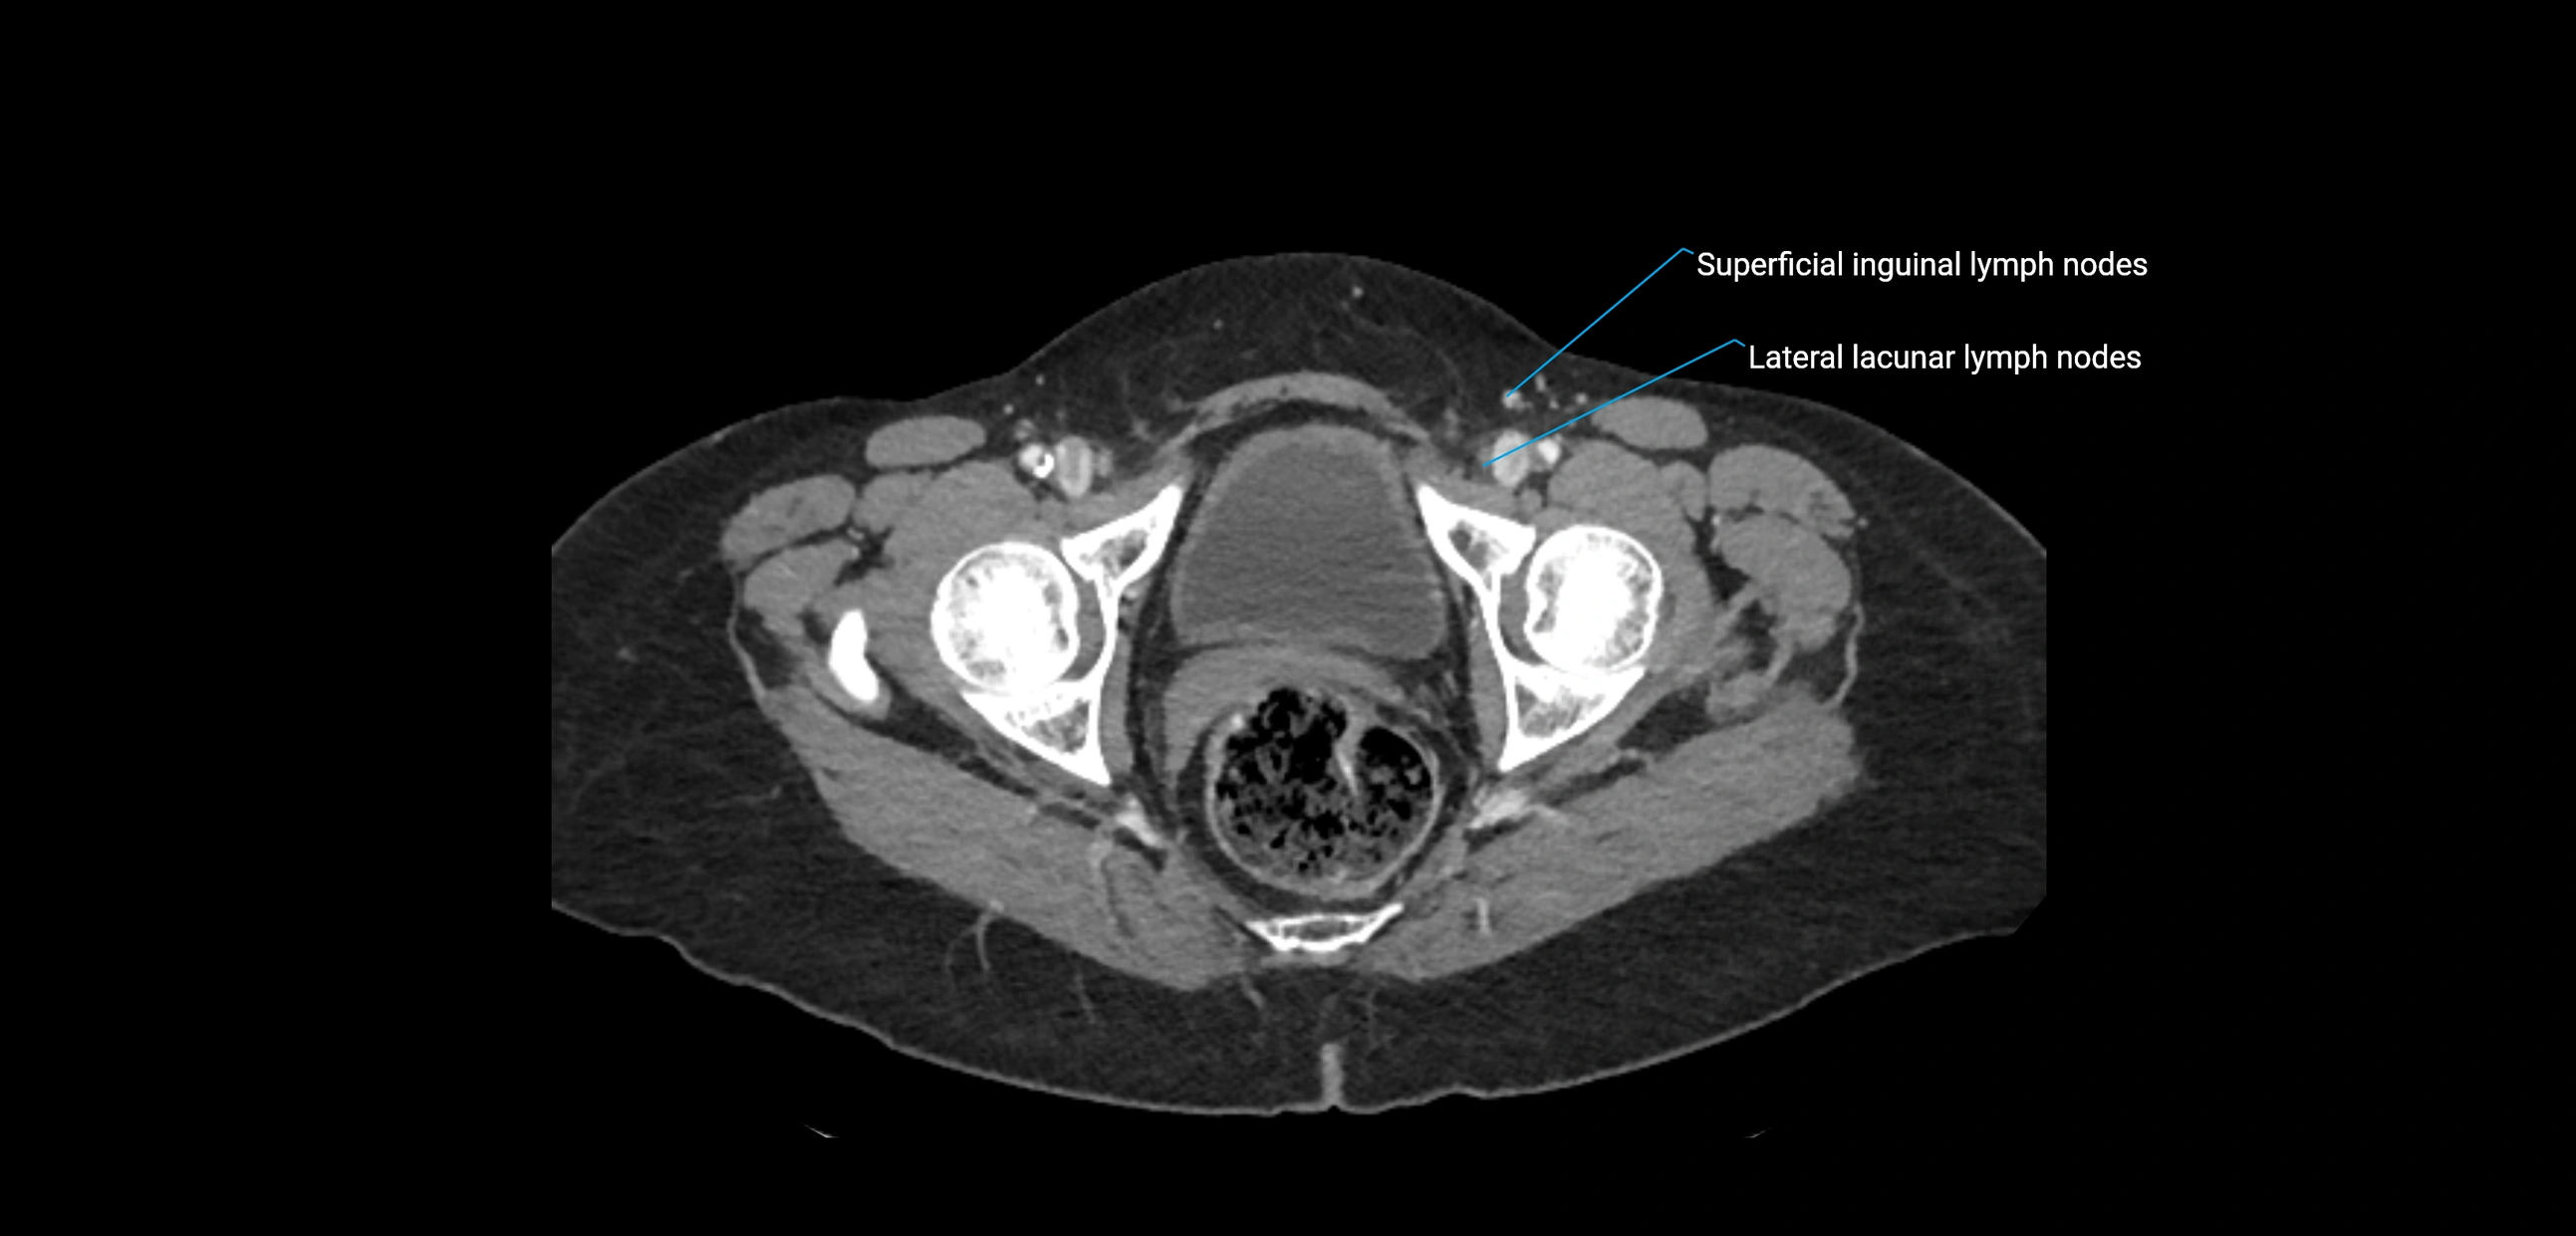

CT Appearance

CT Pre-Contrast:

• Nodes appear as soft-tissue density nodules adjacent to the aorta and IVC

CT Post-Contrast:

• Normal nodes enhance homogeneously

• Malignant nodes may show heterogeneous enhancement, central necrosis, or conglomerate formation

• Size >1 cm short axis is suspicious, though morphology and distribution are equally important